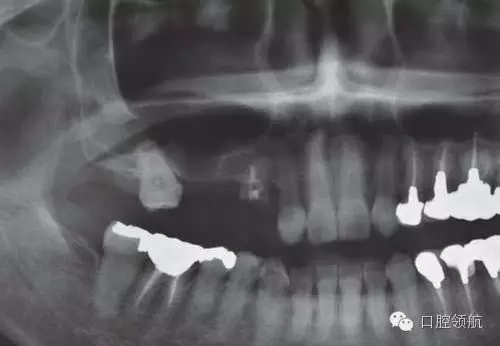

為了在不足的骨量中獲得良好的初期穩(wěn)定性,種植體沒有埋入過深,所以造成軟組織的不足,雖進(jìn)行減張切開縫合,但術(shù)后仍出現(xiàn)牙齦裂開(圖2~圖5)。

圖2 種植體埋入時的口內(nèi)像。因骨板薄,為獲得初期穩(wěn)定性,種植體植入較淺,導(dǎo)致外部連接系統(tǒng)的愈合帽位于牙槽嵴頂上。

圖3 因?yàn)橛厦蔽挥谘啦坩枕斏?,?dǎo)致封閉創(chuàng)口的牙齦組織瓣不足,利用減張切開縫合。

圖4 術(shù)后即刻的曲面斷層影像

圖5 術(shù)后2周愈合帽露出